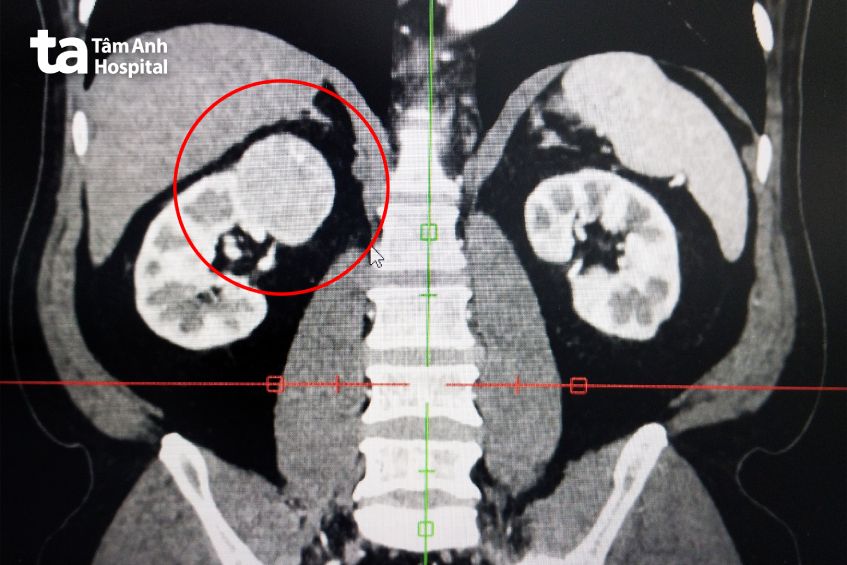

Thạc sĩ bác sĩ Nguyễn Tân Cương, Phó khoa Tiết niệu, Trung tâm Tiết niệu – Thận học – Nam khoa, Bệnh viện Đa khoa Tâm Anh TP.HCM, cho biết qua ảnh chụp cắt lớp vi tính (CT-scanner) nhận thấy khối u thận phải có kích thước 4,5×5,0 cm, ở cực trên thận phải, đậm độ không đồng nhất, u nằm sát tĩnh mạch thận phải (mạch máu đưa máu từ thận về tim), gần tĩnh mạch chủ bụng, ngay bên dưới gan, gần tá tràng (phần ruột non nối với dạ dày) và đại tràng.